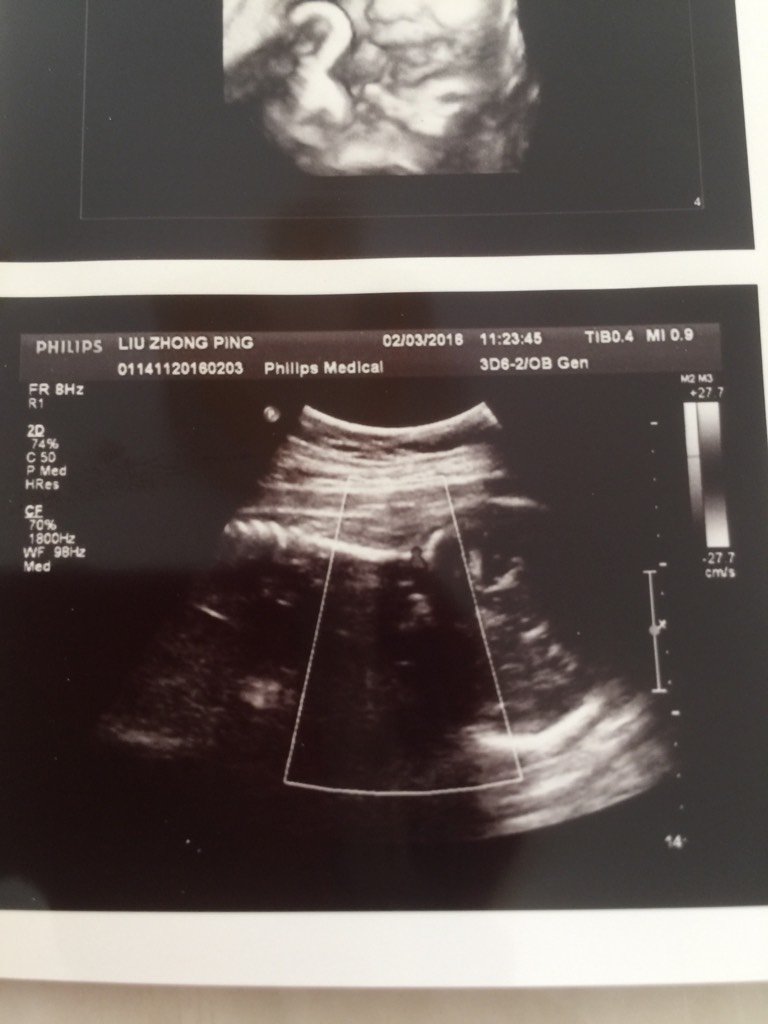

看看我的男宝贝,嘻嘻 看看我的男宝贝,嘻嘻 点击展开 你猜:) 2016-02-05 05:07 为您推荐: 其他回答 恭喜了宝爸宝妈。 看守所的犯人 2016-02-05 06:06 恭喜你了。 ※天天 2016-02-05 05:56 恭喜恭喜了 爱六月 2016-02-05 05:53 恭喜。。。 昕宇.123 2016-02-05 05:47 恭喜(⊙o⊙) 胖花花猫 2016-02-05 05:36 加载更多 相关问题 看看我家宝贝男还是女? 亲爱的们我生了 看看我的宝贝闺女 宝妈们帮我看看我家宝贝是男孩女孩